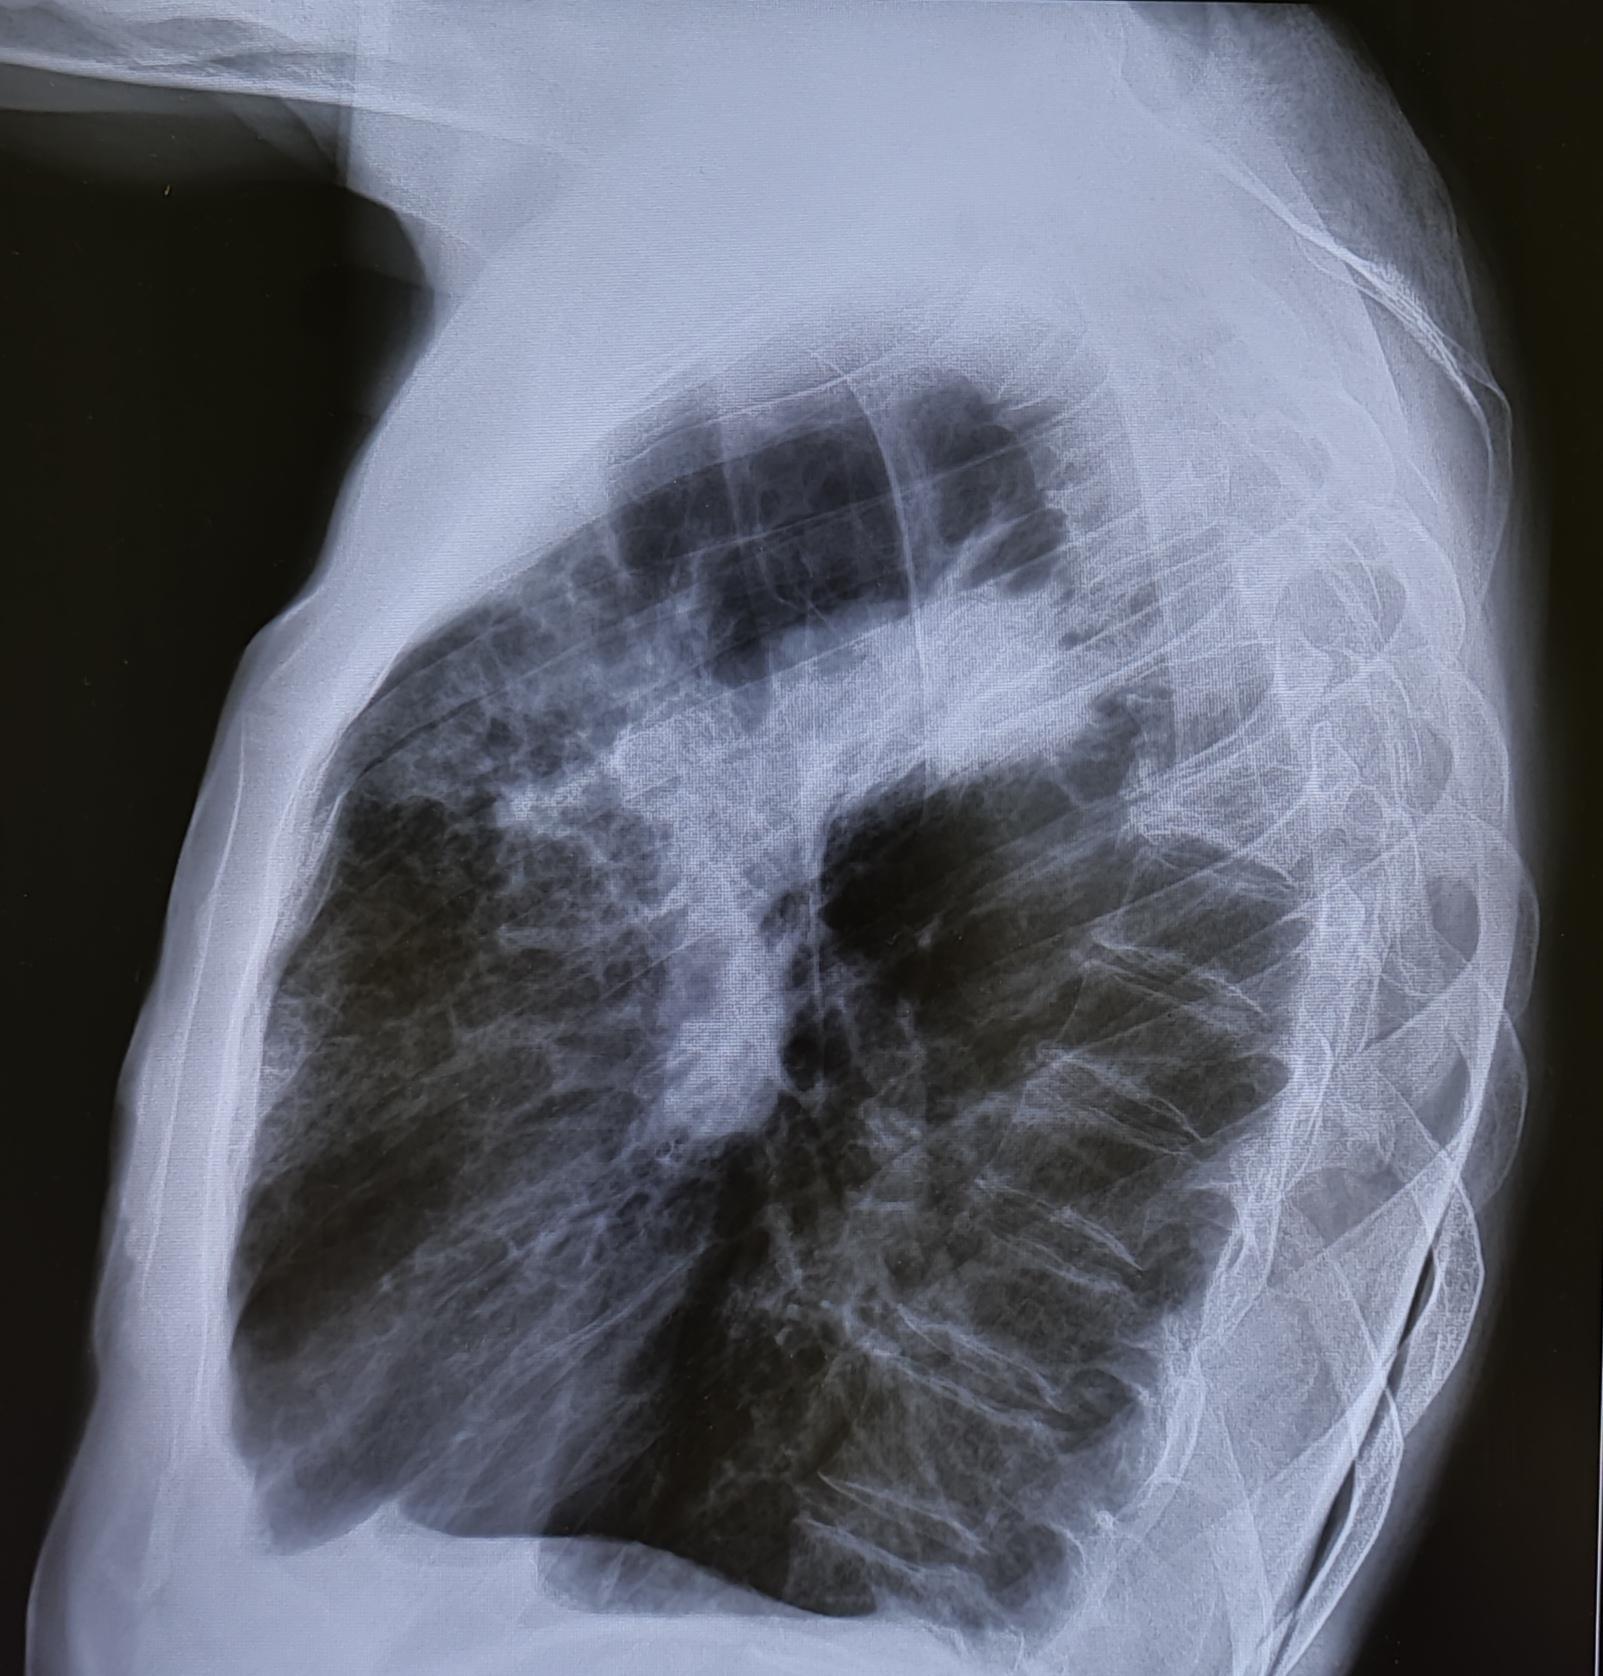

Внебольничная пневмония-рентген

На Р-граммах ОГК в 3х проекциях: На фоне сниженной пневматизации, визуализируются инфильтративные изменения легочной ткани в S2, S3 правого легкого. Легочный рисунок усилен за счет сосудистого компонента. Корень слева-не увеличен, справа-увеличен. Диафрагма не изменена, контуры ее ровные, четкие. Тень сердца обычного расположения не расширена в поперечном размере. Дуга аорты склерозирована. Дегенеративно-дистрофические изменения грудного отдела позвоночника.

Заключение: Правосторонняя бисегментарная S2, S3 пневмония.